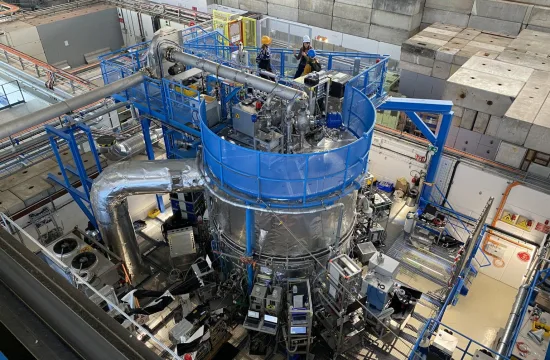

Credit: Boston Children’s Hospital